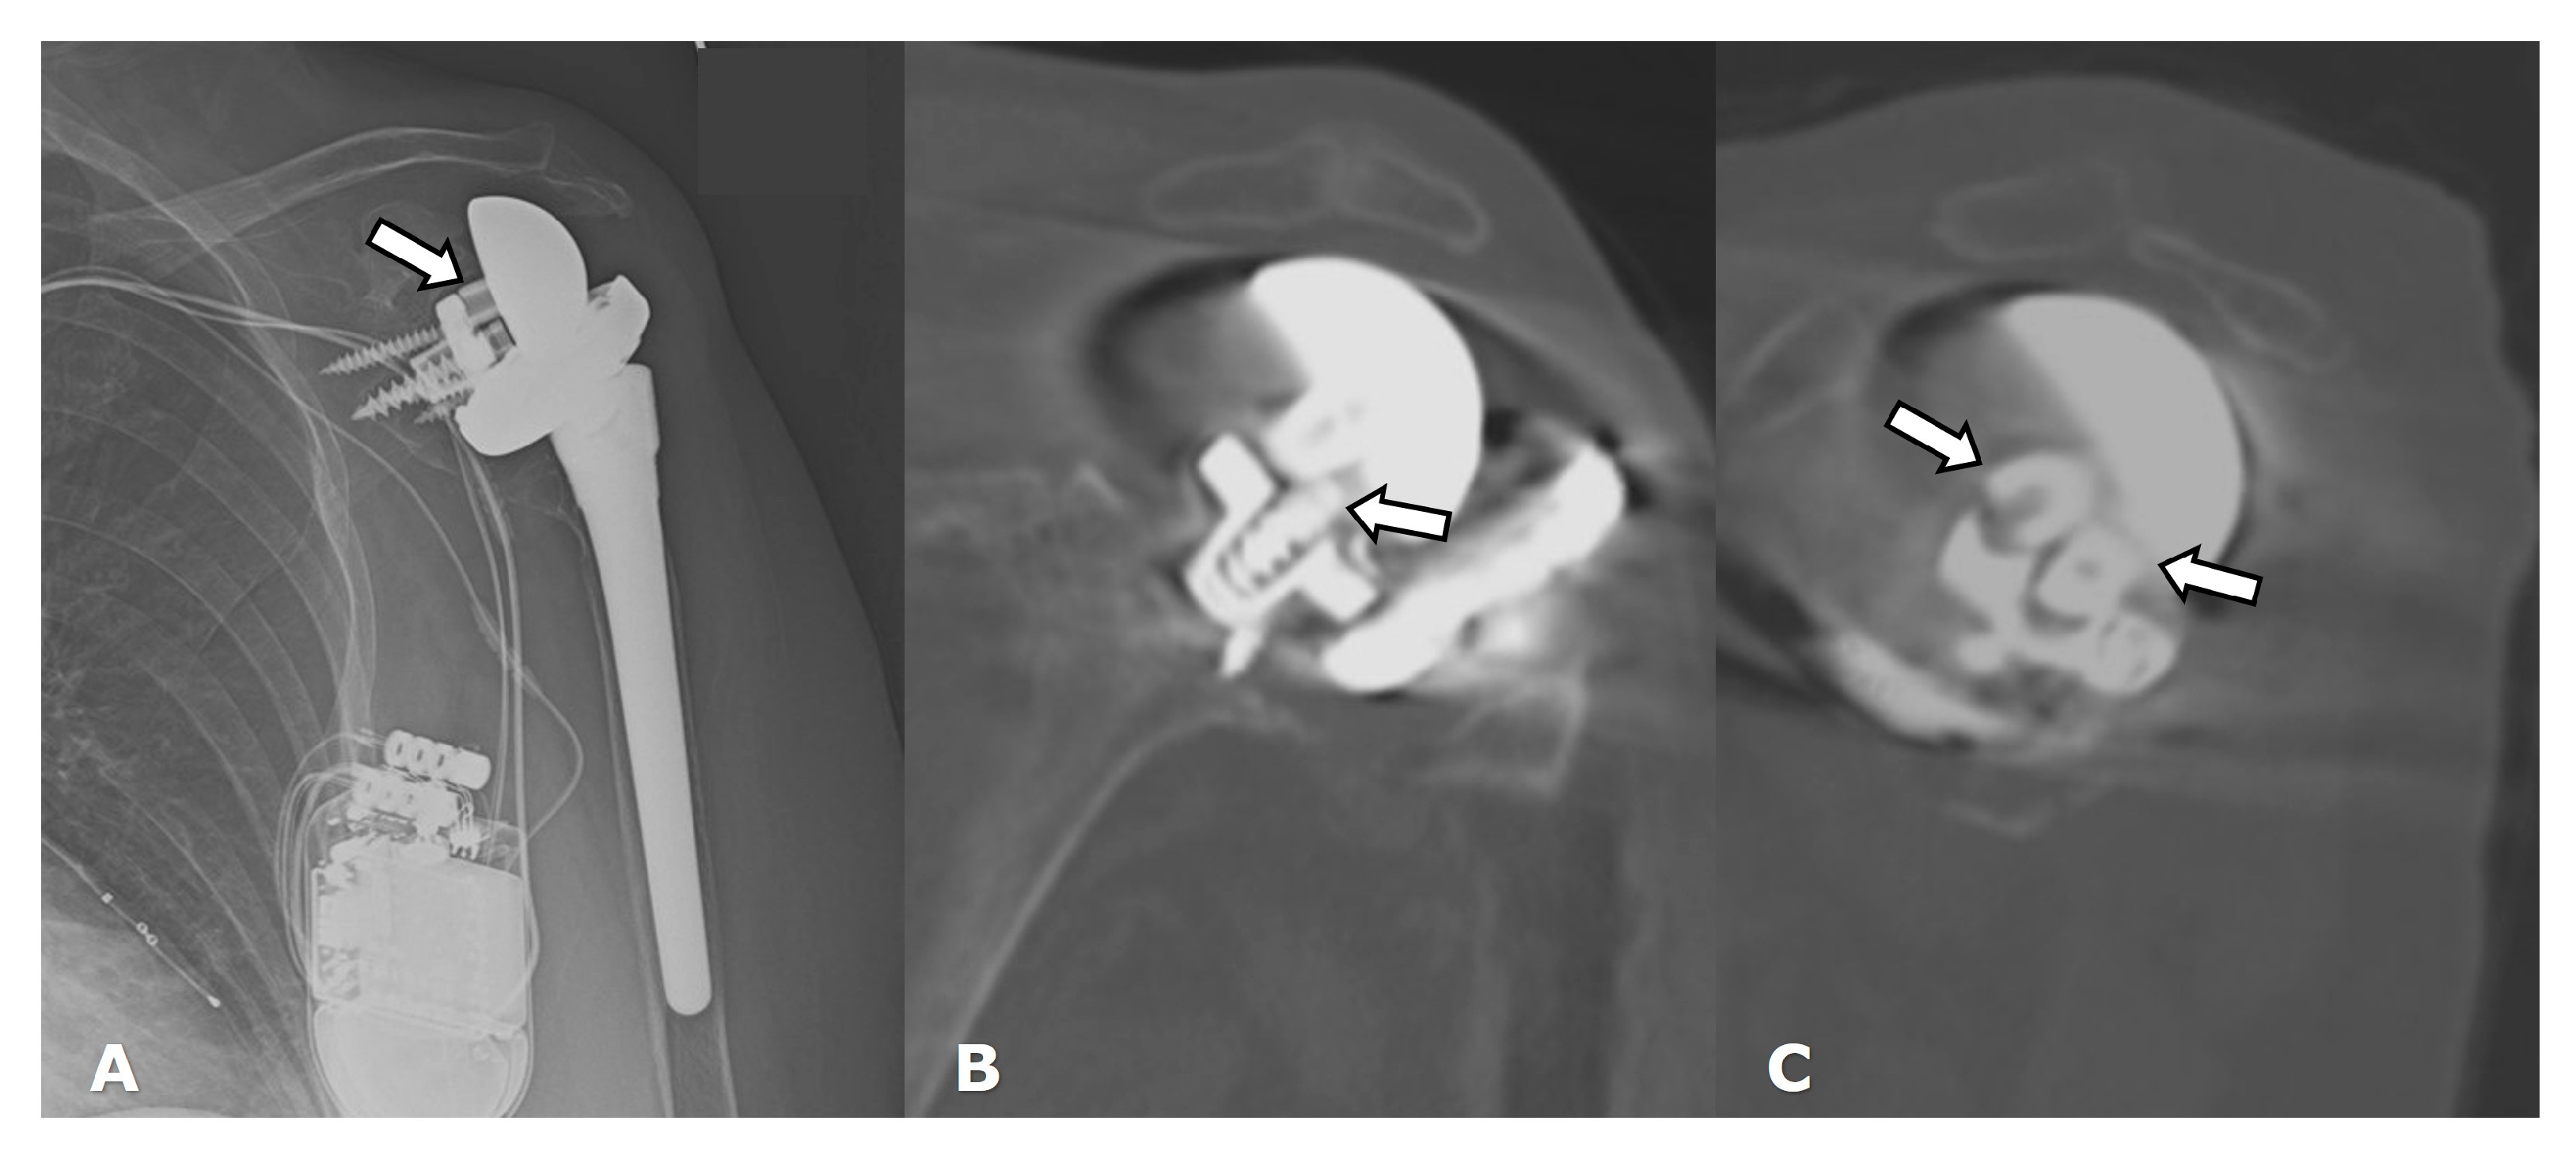

4.2.1. Loosening and Hardware Dissociation

4.3. Unique Complications

5.3. Revision Shoulder Arthroplasty